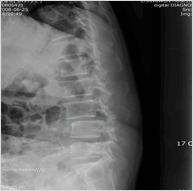

척추체성형술

골다공증이나 악성종양 등에 의한 압박골절이 있을 시 국소마취 후 특수한 바늘을 골절 부위 척추뼈에 삽입하여 골경화물질을 서서히 주입한다. 주입된 골경화물질은 수분 이내에 굳어 통증이 바로 사라진다. 대개의 경우 즉시 통증이 없어져서 수술 후 즉시 보행이 가능하다

척추고정술 - 사진